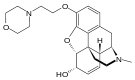

Codeine-dionine family

- Pholcodine (morpholinylethylmorphine)

Structures

| Codeine-dionine family | ||||

Pholcodine Pholcodine |